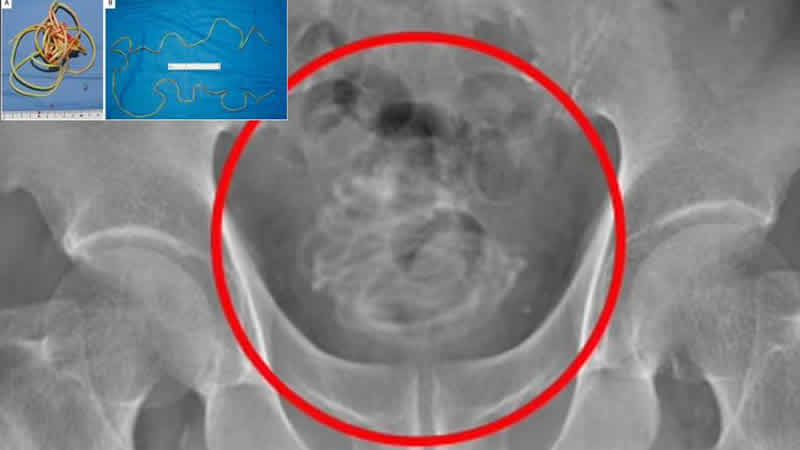

Dokkyo Üniversitesi Tıp Fakültesi’nde röntgen çekildikten sonra, 79 yaşındaki adamın penisinden içeri atlama ipi yerleştirildiğini gören doktorlar şaşkına döndü. İngiliz medyasında yer alan haberlerde hastane çalışanları, “Kariyerimiz boyunca böyle bir şey görmedik” açıklamasını yaptı.

Yapılan zorlu bir ameliyat süreci sonrasında adamın penisinden atlama ipinin çıkarıldığı belirtildi. Atlama ipinin tutma kısımlarının olmadığı ve 2 metreden uzun olduğu belirtildi. İpin, idrar torbasında düğüm olduğu ve bu sebeple ameliyatın riskli geçtiği de belirtildi.

İpin ince olduğuna dikkat çeken doktorlar, ipin düğüm olması sebebiyle idrar torbasına bir delik açarak cerrahi bir müdahale gerçekleştirildiğini de duyurdu. Ameliyatın başarılı geçmesi için idrar torbasının 3-D modelinin yapıldığı ve bu sayede doktorların nasıl müdahale edeceklerinin anlaşıldığı açıklandı.